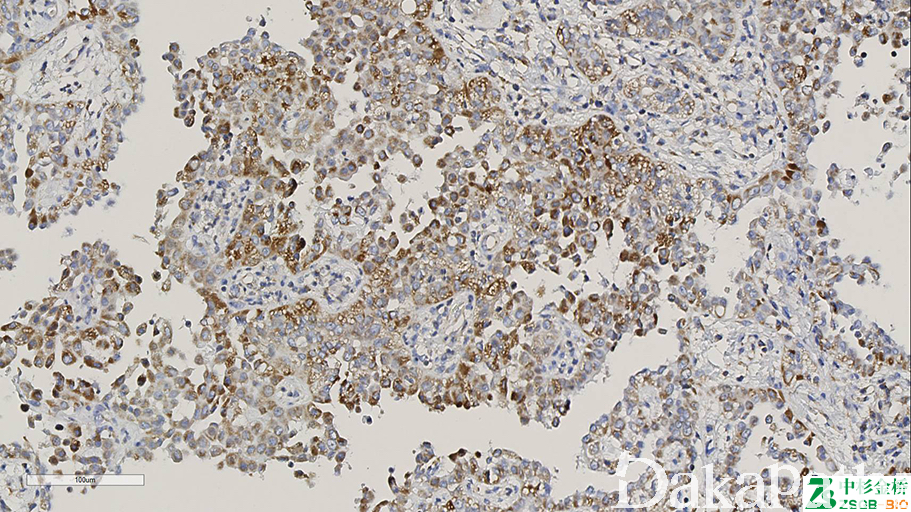

正常细胞普遍核表达 SDHB,异常表达缺失。

信号定位: 胞浆